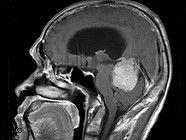

单项选择题男,61岁, 头晕头痛伴行走不稳1月余,请根据所提供图像, 选择最可能的诊断是 ( )

A、淋巴瘤

B、转移瘤

C、胶质瘤

D、髓母细胞瘤

E、(天幕切迹缘)脑膜瘤